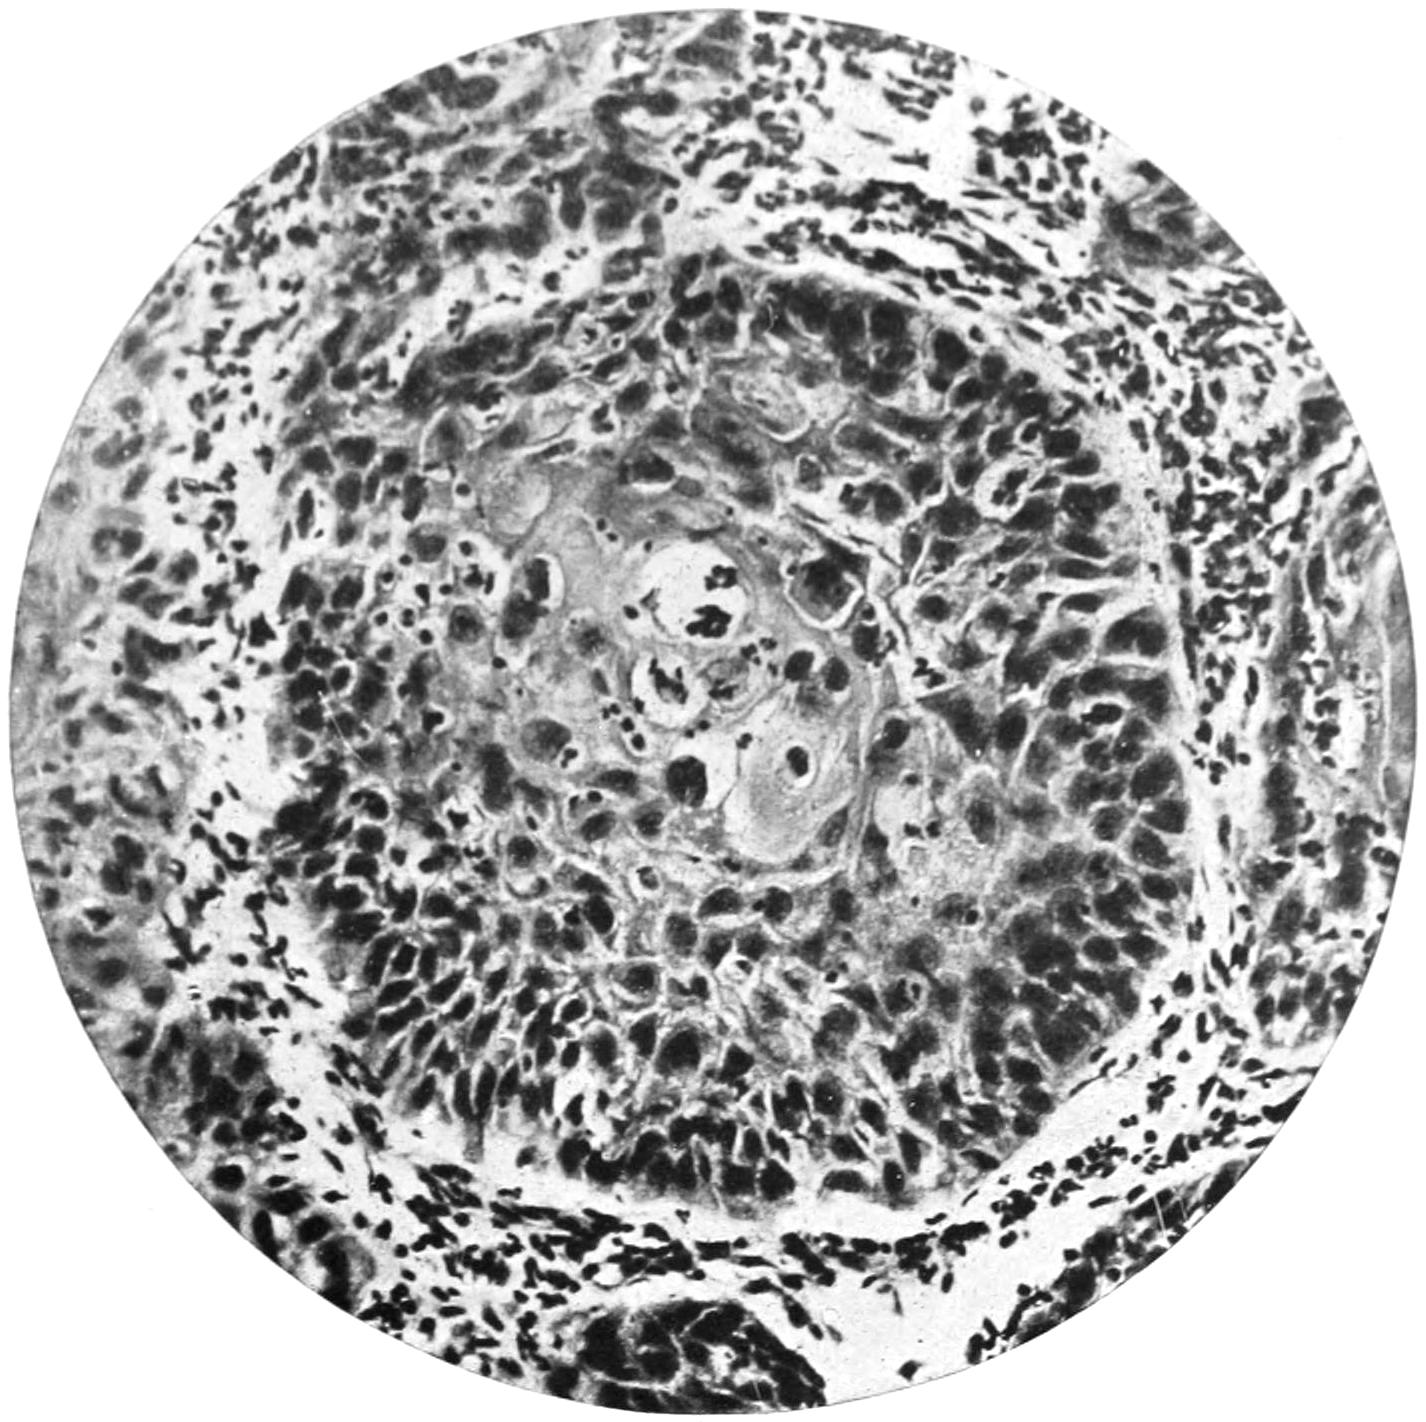

PLATE I

Fig. I.

Fig. II.

Fig. III.

Fig. IV.

Fig. V.

Fig. VI.

Fig. VII.

Fig. VIII.

DRAWN BY J. N. Z. CHASE

PLATE I.

BLOOD.

(Ehrlich triple stain.)

(Prepared by Dr. I. P. Lyon.)

Fig. I. TYPES OF LEUCOCYTES.

a. Polymorphonuclear Neutrophile. b. Polymorphonuclear Eosinophile. c. Myelocyte (Neutrophilic). d. Eosinophilic Myelocyte. e. Large Lymphocyte (large Mononuclear). f. Small Lymphocyte (small Mononuclear).

Fig. II. NORMAL BLOOD.

Field contains one neutrophile. Reds are normal.

Fig. III. ANÆMIA, POST-OPERATIVE (secondary).

The reds are fewer than normal, and are deficient in hæmoglobin and somewhat irregular in form. One normoblast is seen in the field, and two neutrophiles and one small lymphocyte, showing a marked post-hæmorrhagic anæmia, with leucocytosis.

Fig. IV. LEUCOCYTOSIS, INFLAMMATORY.

The reds are normal. A marked leucocytosis is shown, with five neutrophiles and one small lymphocyte. This illustration may also serve the purpose of showing the leucocytosis of malignant tumor.

Fig. V. TRICHINOSIS.

A marked leucocytosis is shown, consisting of an eosinophilia.

Fig. VI. LYMPHATIC LEUKÆMIA.

Slight anæmia. A large relative and absolute increase of the lymphocytes (chiefly the small lymphocytes) is shown.

Fig. VII. SPLENO-MYELOGENOUS LEUKÆMIA.

The reds show a secondary anæmia. Two normoblasts are shown. The leucocytosis is massive. Twenty leucocytes are shown, consisting of nine neutrophiles, seven myelocytes, two small lymphocytes, one eosinophile (polymorphonuclear) and one eosinophilic myelocyte. Note the polymorphous condition of the leucocytes, i. e., their variations from the typical in size and form.

Fig. VIII. VARIETIES OF RED CORPUSCLES.

a. Normal Red Corpuscle (normocyte). b, c. Anæmic Red Corpuscles. d-g. Poikilocytes. h. Microcyte. i. Megalocyte. j-n. Nucleated Red Corpuscles. j, k. Normoblasts. l. Microblast. m, n. Megaloblasts.

The value of a careful blood examination is well illustrated by Plate I, prepared by Dr. Irving P. Lyon, in which are displayed the alterations of greatest interest to the surgeon.